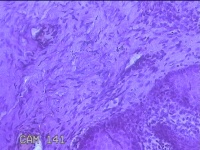

舌头肿物

性别

女

年龄

25岁

临床诊断

一般病史

无

标本名称

大体所见

灰白粉红色肿物0.7x0.5x0.2cm一个,表面光滑。

纤维性息肉